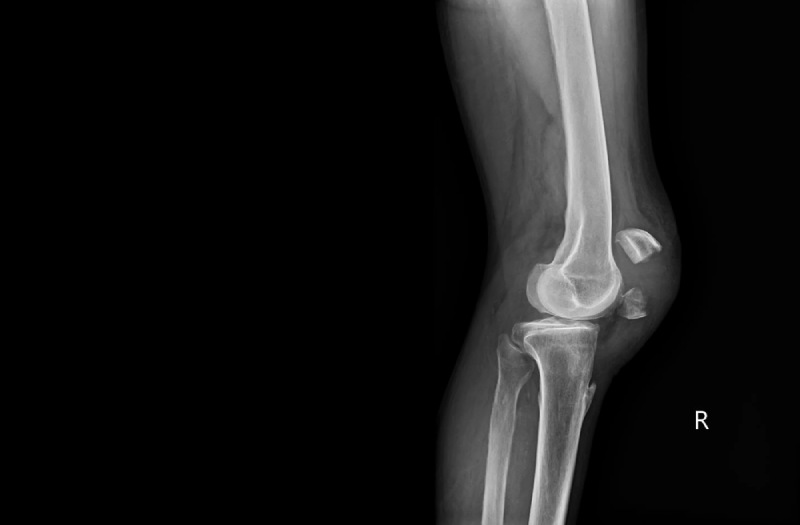

Để xác định nguyên nhân đau đầu gối khi vận động, bác sĩ sẽ xem xét các triệu chứng sưng, đau, nhạy cảm, ấm, bầm tím ở gối; đồng thời kiểm tra khả năng chuyển động của khớp. (4)

Tiếp đó, người bệnh có thể được chỉ định thực hiện xét nghiệm:

Đầu gối bị đau khi vận động lâu này nên được thăm khám sớm để kịp thời phát hiện bệnh lý tiềm ẩn, phòng ngừa biến chứng. Bạn nên ưu tiên những địa chỉ được trang bị máy móc hiện đại, chẳng hạn như Bệnh viện Đa khoa Tâm Anh. Đây là cơ sở ứng dụng hệ thống chụp CT 768 lát cắt Somatom Drive (Siemens – Đức), hệ thống cộng hưởng từ thế hệ mới MAGNETOM Amira BioMatrix (Siemens – Đức), hệ thống X-quang treo trần DigiRAD-FP (Hàn Quốc), máy đo loãng xương bằng tia X Horizon W (Hologic – Mỹ),… giúp hỗ trợ chẩn đoán bệnh chính xác và nhanh chóng.